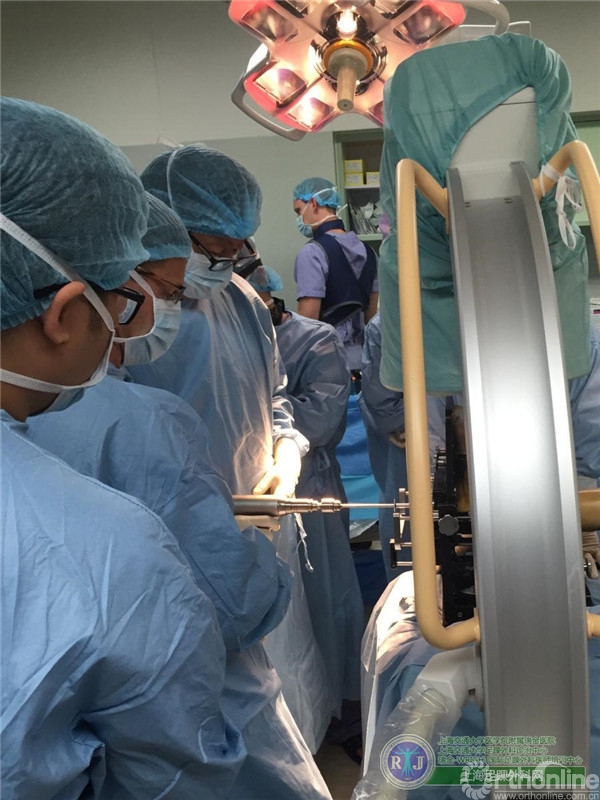

上海瑞金医院骨科足踝外科团队于2015年10月28日上午成功对该患者实施了第三代全踝关节假体(INBONE® II. Wright.)置换手术,手术过程非常顺利。手术中首先清理踝关节内外侧炎性组织及骨赘,将患足置于专门的定制支架中,在透视下反复调整足踝及导针位置,力求最高精确度。在截骨导板的定位下进行踝关节胫骨及距骨的截骨,试样假体大小,置入合适匹配的踝关节假体及垫片完成全踝关节假体的置换,全程手术时间90分钟。完成的全踝关节假体置换位置精确,假体设计稳定牢固,踝关节内外侧软组织平衡,达到了预期的效果。术后患者恢复良好,手术取得圆满成功。患者在休养五周左右以后可以下地行走,去除踝关节炎疼痛畸形的同时能够保留踝关节的活动度,为生活和工作提供极大便利。